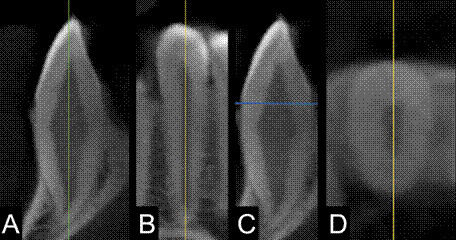

The degree of sexual dimorphism exhibited by teeth plays a crucial role in sex estimation, particularly as they are frequently found well-preserved. This study aimed to assess the presence of sexual dimorphism in the roots of upper lateral incisors, upper canines, and lower canines using cone-beam computed tomography (CBCT), and to develop and validate a formula for sex estimation. Linear measurements, surface area, and volumetric measurements were conducted on a total of 140 CBCT volumes (100 for evaluation and 40 for validation) from a Brazilian population, with an equal distribution of sexes, aged between 18 and 50. Statistical analysis involved the Kolmogorov-Smirnov test, unpaired t-test with Welch correction, Pearson's correlation test, logistic regression using the Backward Stepwise method, sieve test, Kappa test, intraclass correlation coefficient, and statistical power calculation (α=0.05). The three teeth showed sexual dimorphism, with measurements from males being statistically larger. Notably, only the formulas for the lower canine met the Mohan and Daubert admissibility criteria. The formula for assessing a sound root used included the mesiodistal diameter, axial cross-section volume, and two-thirds of the coronal cross-section volume. For evaluating reduced root length, the formula incorporated the mesiodistal diameter and axial cross-section volume. The accuracy of the lower canine formulas for sound and reduced root length were 89% and 87%, respectively. After validation, both formulas achieved an accuracy of 85%. In conclusion, the models combining measurements from the lower canine can be applied as a complementary method for sex estimation.